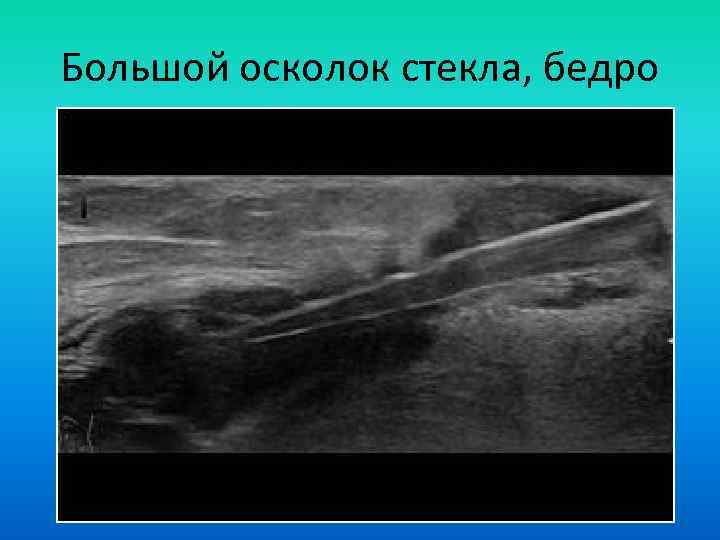

Большой осколок стекла, бедро Большой осколок стекла, бедро